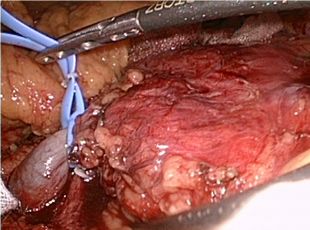

治療に関しては、当院では腹腔鏡下にて手術を施行しています。

症例.(腎細胞がん(右))       症例.(腎細胞がん(左))

腹腔鏡